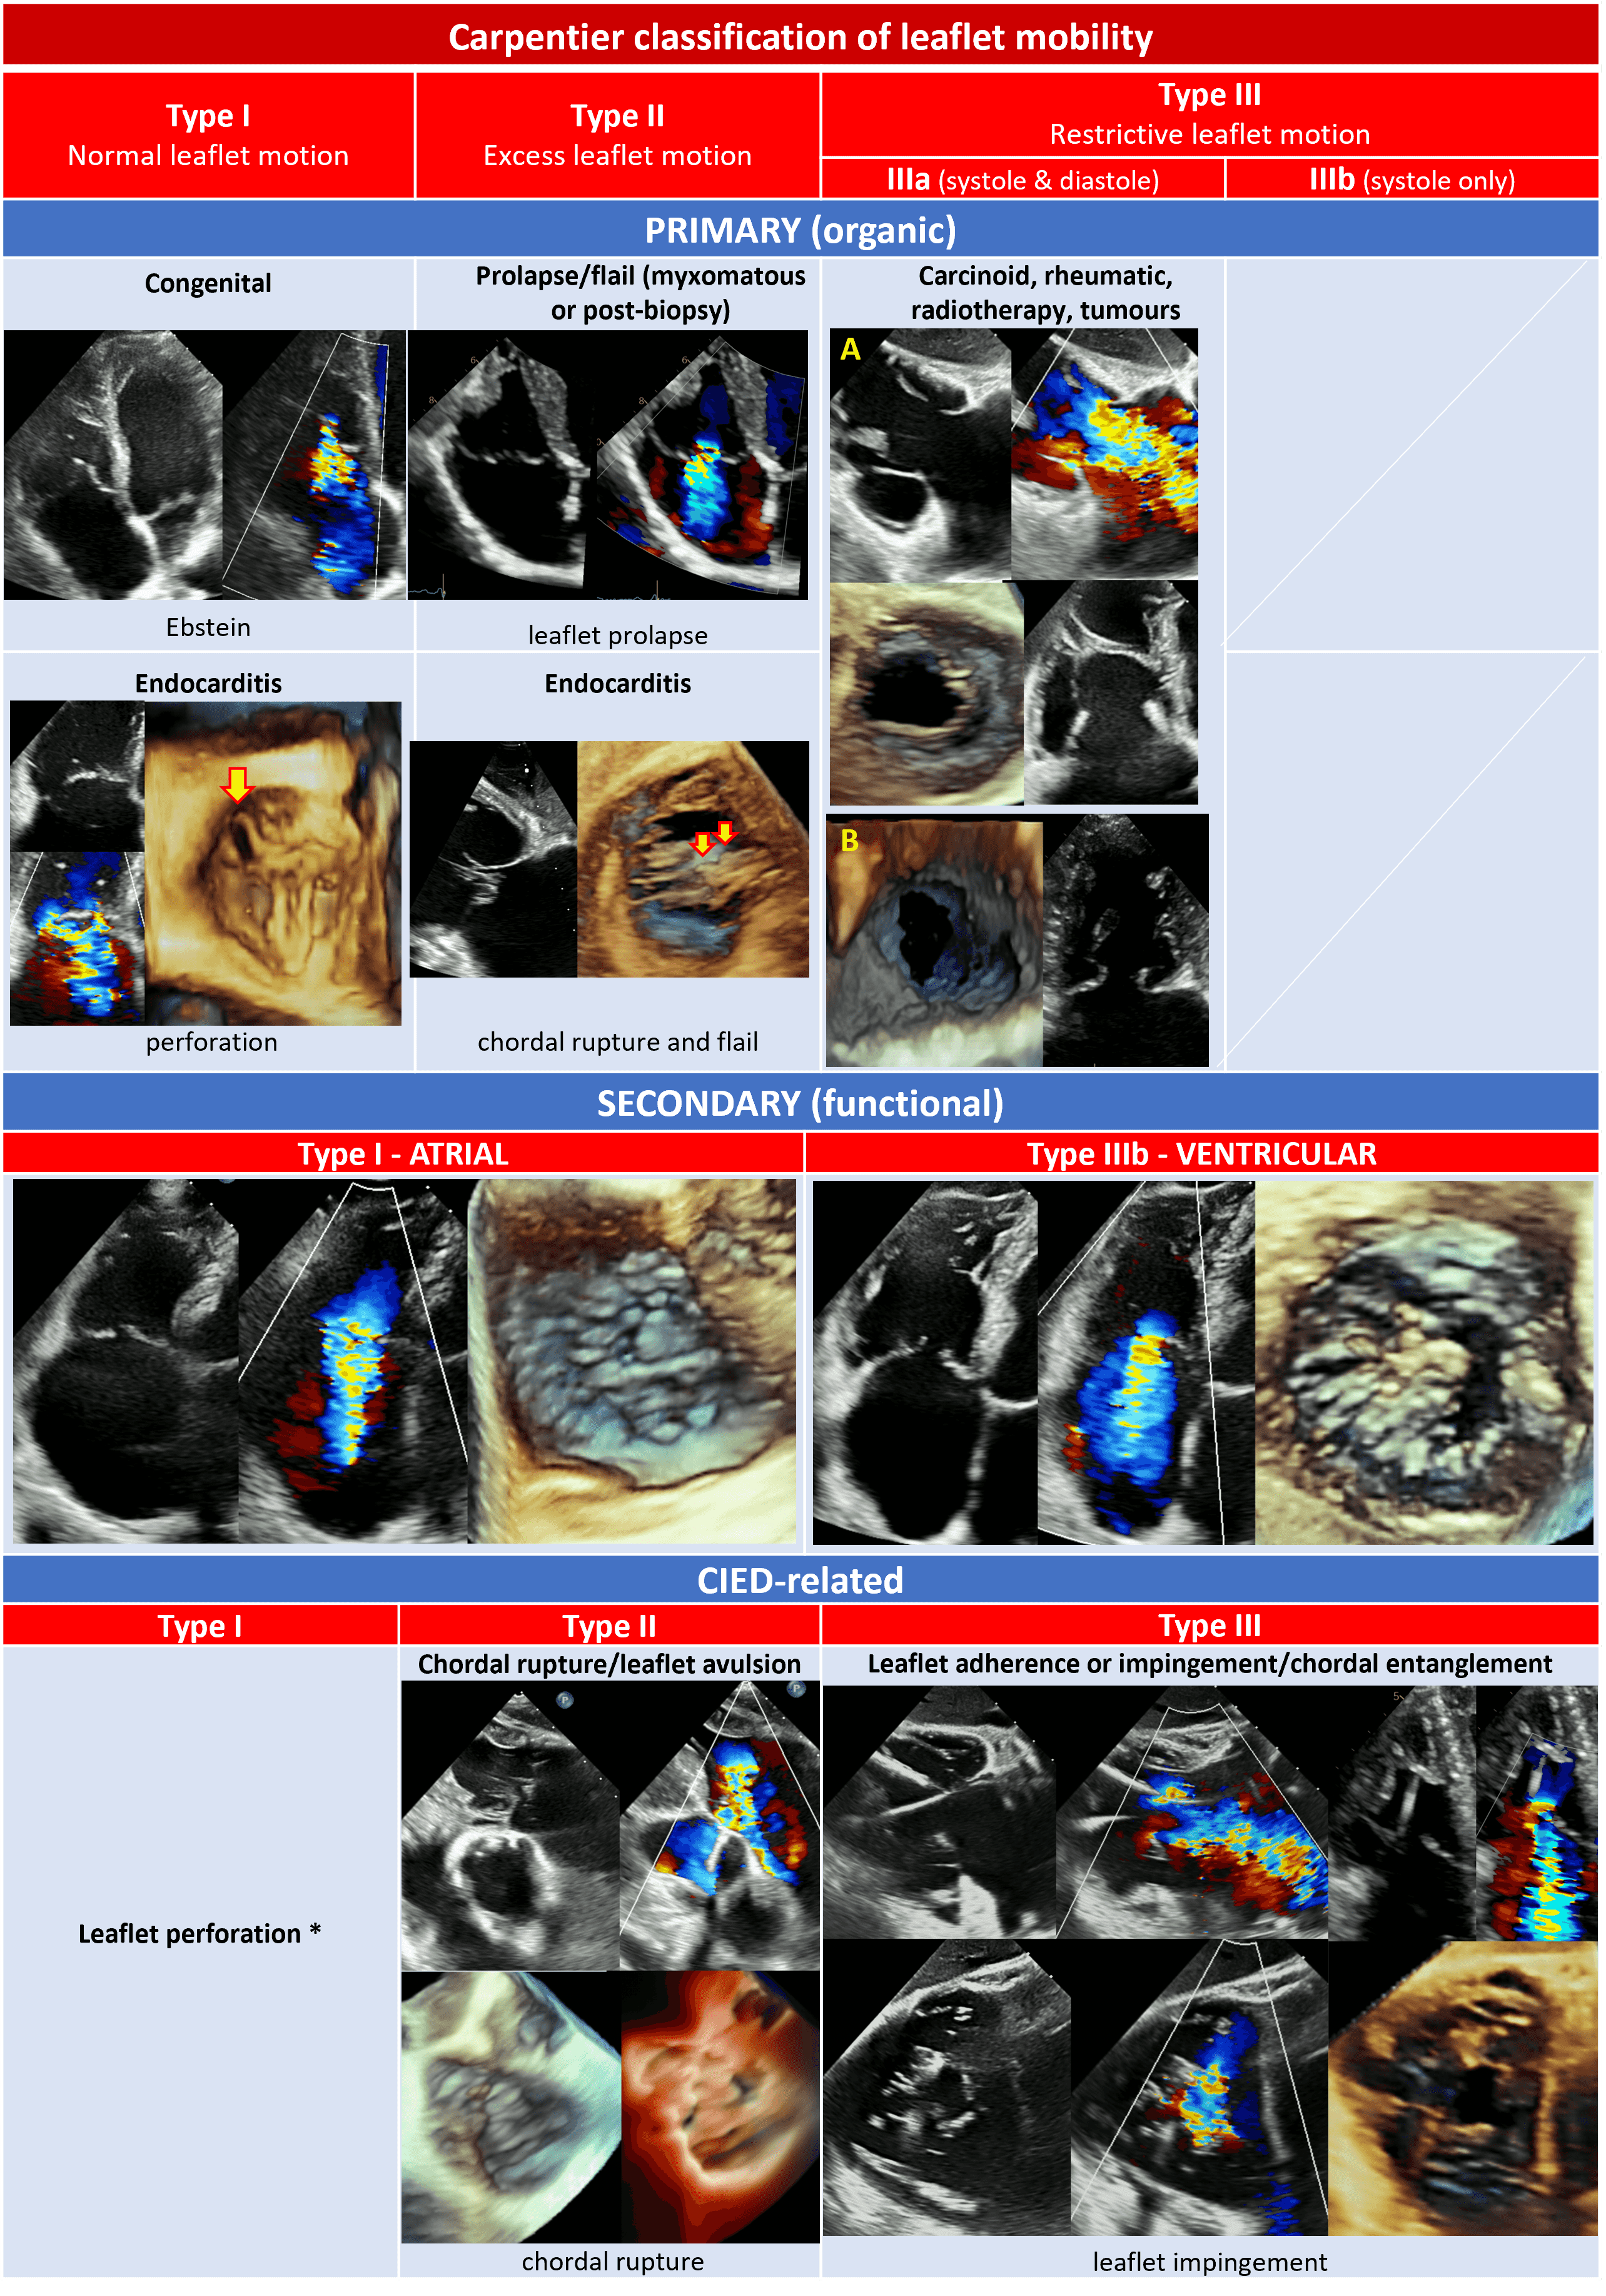

Here follow the procedural steps of TEER for TV, altogether with the main required TEE views (Fig. 8) [43, 59, 129].

Fig. 8.Steps of intraprocedural imaging. (A,B) Insertion of the steerable guide catheter into the right atrium. (C–E) Advancement of the clip delivery system through the steerable guide catheter into the right atrium and steering towards tricuspid valve plane. (F) Axial alignment of the clip delivery system. (G) Clip rotation and alignment to the coaptation line. (H,I) Leaflet grasping. (L–N) Check of adequate leaflet tissue grasping. (O,P) Assessment of residual TR. (Q) Clip deployment. (R) advancement of a second clip into the right atrium.

(1) Insertion of the steerable guide catheter into the RA (Fig. 8A,B): ME bicaval or modified bicaval (with TV in sight), TG LAX with entry point of IVC into RA in the view, 3D view of RA.

(2) Advancement of the clip delivery system through the steerable guide catheter into the RA and steering towards TV plane (Fig. 8C–E): same views of the first step plus the inflow-outflow view (or intercommissural view) with biplane (or cross-plane) mode for the steering manoeuvre towards the target lesion. The interaction of the clip delivery system and the clip itself with the interatrial septum have to be carefully followed to avoid a perforation of the interatrial septum. As the basic principle of TEER for TV is to approximate the mural leaflet to the septal one, which works as an anchor, the inflow-outflow view (ME or DE) is fundamental because, together with the biplane-derived 4 chamber views, it allows to entirely span the septal leaflet and to guide the clip in anterior-posterior and septal-lateral directions towards the target lesion.

(3) Axial alignment of the clip delivery system (Fig. 8F): ME or DE inflow-outflow views with biplane mode, TG views. The trajectory of the clip delivery system towards the target lesion should be properly adjusted so that the clip results perpendicular to the TV plane.

(4) Clip rotation and alignment to the coaptation line (Fig. 8G): TG with biplane mode (simultaneous assessment of SAX and LAX).

(5) Leaflet grasping (Fig. 8H,I): ME or DE inflow-outflow views with biplane mode with the primary plane positioned perpendicular to the clip arms showing the clip position along the coaptation line. As already mentioned, the inflow-outflow view is crucial for a successful tricuspid TEER procedure as it permits a quick and effective localization of the clip along the entire coaptation line with the septal leaflet.

(6) Check of adequate leaflet tissue grasping (Fig. 8L–N): TG with biplane mode (simultaneous assessment of SAX and LAX), ME or DE inflow-outflow views with biplane mode, ME 4-chamber and DE 2-chamber views, 3D imaging from any window and with additional use of real-time MPRs. The quality check of leaflet grasp is based on several factors: restriction of leaflet motion and clip stability on 2D imaging, adequate tissue bridge on 3D imaging, and TR reduction with colour-Doppler.

(7) Assessment of residual TR (Fig. 8O,P) and trans-valvular gradient (

(8) Clip deployment (Fig. 8Q): views of the previous step. After clip deployment a reassessment of clip stability and residual TR is necessary; the clip delivery system is then safely withdrawn under echocardiographic guidance unless another clip is needed (Fig. 8R).